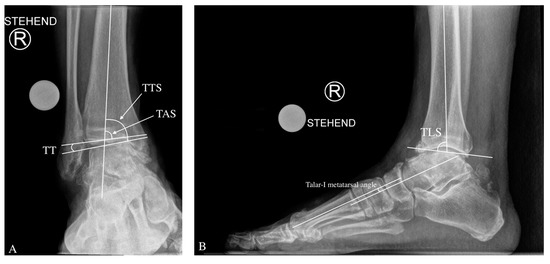

On the anteroposterior view, the medial distal–tibial angle (MDTA: normal range 93.3 ± 3.2 degrees, also known as tibial anterior surface angle (TAS) formed by the mechanical axis of the tibia and the tangent of the tibial plafond on the medial side of the ankle (Figure 1). The MDTA in varus ankle OA is <90° and is overcorrected postoperatively over the physiological average by 2–5°.

Angles for the Radiological Evaluation of a Varus Ankle Osteoarthritis. On the anteroposterior view, tibial anterior surface angle TAS (also known as medial distal tibial angle MDTA) tibiotalar surface (TTS) and talar tilt (TT) angle are shown (A). On lateral ankle radiograph, the tibial lateral surface angle (TLS) is assessed (B). The talar-1st metatarsal angle gives us a hint about the amount of midfoot deformity, both on lateral and dorsoplantar view (B,C). Inframalleolar deformity can be evaluated on the Saltzman view by measuring the hindfoot alignment view (HAV) angle (D).

Further, in the ap view, the tibiotalar surface angle (TTS; normal range; 87.2 ± 2.8 degrees) is measured [13,14]. The TTS in varus ankle OA is <84.4°.

The talar tilt (TT) angle is used to assess tibiotalar congruence. The tibial articular surface and the talar articular surface on the AP X-ray produce this angle. It is usually less than 4 degrees [15].

On a lateral ankle radiograph, the tibial lateral surface (TLS) angle is measured using the mechanical axis of the tibia and a line passing across the ends of the tibial articular surface in a lateral view, with a typical range of 83.0 ± 3.6 degrees [19].

Inframalleolar deformity can be evaluated on the (Saltzman view) by measuring the hindfoot alignment view (HAV) angle between the anatomical axis of the tibia and the axis of the calcaneus. Normally, HAV has a value of 0–5° [20]. The Saltzman view can also be useful for detecting subtalar malalignment [21].

The lateral talar-1st metatarsal angle is an index of midfoot deformity magnitude. Pes planus is defined as a downward convex angle larger than 4° [22].